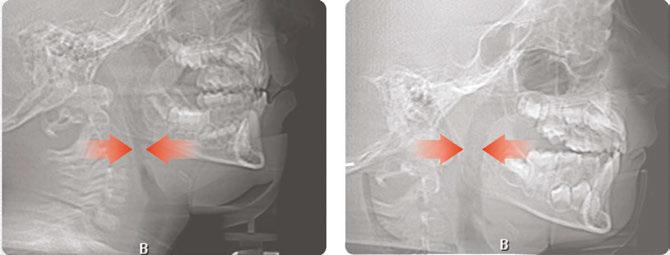

Over 10 years ago, we began Orthotropic® treatment for a 5 year, 3-month-old boy with a diagnosis of Pierre-Robin Sequence, Obstructive Sleep Apnea (OSA), and Failure to Thrive (Figure 1). With lack of forward development of the face com-

12 Pediatric Dental Practice US Volume 1 Number 1 PEDIATRIC PERSPECTIVE

monly seen in Pierre-Robin patients, his airway was compromised, resulting in OSA. The Failure to Thrive diagnosis likely resulted from insufficient growth hormone being released during the deeper stages of sleep. This treatment began before any permanent teeth erupted. Our goal was to eliminate OSA.

Orthotropics® uses removable appliances to laterally expand the upper arch while simultaneously advancing the upper anterior teeth to their proper place in the face. Then the mandible is developed forward. Orthotropics® is my preferred treatment in cases like this because it negates the head gear-effect producing better facial balance5 and also can result in substantial airway improvements (Figure 2).6

Figure 1: Pretreatment gallery Figure 3: Today, he’s a tennis player Figure 2: Pre- and posttreatment airways